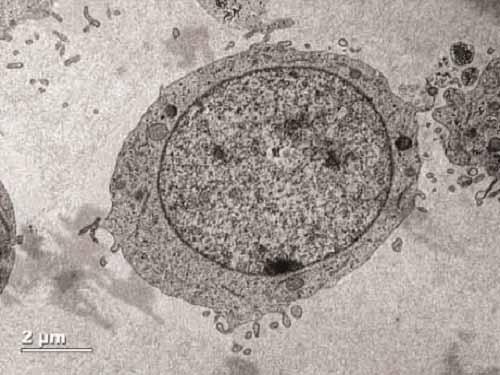

These CD34-positive cells can give rise to all the various types of blood components--but they're not the only ones with this ability. Some cells that don't express this surface marker can do the same; however, CD34-negative cells in circulation aren't as good at finding their way to the bone marrow. Thus, doctors have tended to focus on CD34 selection as an easy and effective means of enriching for high-potential blood stem and progenitor cells despite the longstanding mystery of the normal biological function of CD34.

Merzaban and her colleagues revealed one of the functions of this protein by first testing different populations of blood-forming cells for their ability to bind adhesion molecules. They showed that only those cells expressing CD34 could do so, and an unbiased protein screen revealed that CD34 itself was responsible for this binding. Knocking down the protein confirmed CD34's essential role in cell migration.